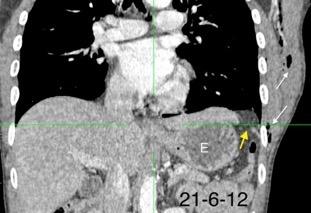

33. ENF. TORACOABDOMINAL. SEUDOQUISTE PANCREÁTICO

3 rasgos: Conexión entre mediastino y lesión pancreática. Derrame pleural Hallazgos de pancreatitis. Matsusue E et al.Three cases of mediastinal pancreatic pseudocysts. Acta Radiol Open. 2016 .